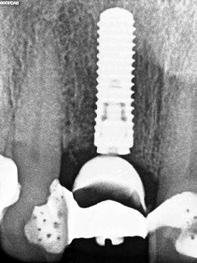

1. ábra: Műtét előtti fogászati panorámafelvétel, amelyen a hiányzó felső állcsont jobb első premolárisát és a szabad véggel rendelkező hidat láthatjuk. — 2. ábra: Az implantátum méreteinek megtervezése CBCT-vel. 3. ábra: Bukkális lágyrészdefektus. — 4. ábra: A biológiai szélesség értékelése a vertikális lágyszövetvastagság alapján. 5. ábra: Palatinális „tekercslebeny” – Palatal roll flap. — 6. ábra: Bredent medical copaSKY 4x10 implantátumbeültetés. 7. ábra: Szubkresztális implantátumbeültetés a várható biológiai szélességnek megfelelően.

(2. ábra). A lágyszövetek értékelése Seibert szerinti I. osztályú csontdefektust állapított meg (3. ábra), ezért a beavatkozáskor palatinális „tekercslebenyt” preparáltunk (palatal roll flap), és implantációt végeztünk, hogy kompenzálni tudjuk a bukkális lágyszövet-behúzódást. Megmértük a vertikális lágyszövetvastagságot, és úgy terveztük, hogy a szubkresztális implantátum beültetése összhangban legyen a biológiai szélesség kialakulásával a transzgingivális gyógyulási periódus alatt (4. ábra)

Az eljárást helyi érzéstelenítés mellett végeztük (4%-os articaine-hidroklorid 1:100 000 adrenalinnal). Papillakímélő, U alakú palatális bemetszést végeztünk, teljes vastagságú nyálkahártyalebeny preparálás történt, a lebenyt bukkálisan feltekertük (5. ábra). A lebeny bukkálisan feltekert részén de-epitelizációt végeztük el, amellyel kompenzálni tudtuk a bukkális lágyszöveti defektust. Szakaszos előfúrást végeztünk, és a bredent copaSKY 4x10 implantátumot 30 Ncm behajtási nyomatékkal helyeztük be (6. ábra). Az implantátumot 1 mm-re szubkresztálisan helyeztük be, hogy később szélesebb emergenciaprofilt tudjunk kialakítani (7. ábra). Az egyedi ínyformázó úgy készült, hogy kompozitot vittünk fel a titánbázisra, és így formáztuk a lágyszöveteket a transzgingivális gyógyulási fázis során (8. ábra). Az egyéni ínyformázó tulipán formájú, hogy kialakítsa a kívánt emergenciaprofilt. A lágyszövetet feszülésmentesen zártuk #6/0 nem felszívódó, monofil fonallal (Optilene, B. Braun Deutschland; 9. a–b. ábra). Posztoperatív röntgenfelvétel készült, ami alapján az implantátum a szomszédos fogakkal párhuzamos elhelyezést mutatott (10. ábra). Posztoperatív utasításokat adtunk a páciensnek a műtéti terület körüli szájhigiénia fenntartása érdekében. A beavatkozást követő egy héttel a varratokat eltávolítottuk, és a kezelt terület kielégítő gyógyulást mutatott (11. ábra). A 4 hónap utáni késleltetett terhelést a páciens kívánsága szerint terveztük.

10. ábra: A műtét utáni radiológiai felvétel.